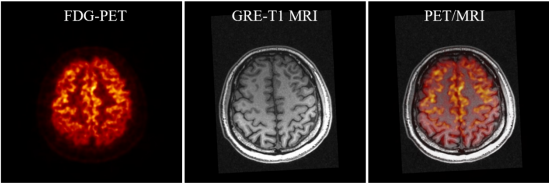

SIAT bPET和联影uMR790 3T磁共振成像系统上同时取得的人脑PET/MRI图像

杨永峰介绍道,与国外商业磁兼容脑PET成像仪器相比,SIAT bPET的效率提高了近2倍(从7.2%到14%),平均体分辨率提高了30倍以上(从约64mm3到2mm3)。同时,SIAT bPET采用了创新的电子学和磁兼容设计,使得磁共振成像对PET成像的影响几乎可以忽略不计,PET成像对磁共振成像图像信噪比的影响小于5%,满足同时召开PET/MRI成像的尖端科研需求。

据分析,PET和MRI都是脑科学研究和脑疾病诊断的重要工具,PET的高灵敏度、高定量精度功能代谢成像和MRI的高空间分辨率、高软组织对比度解剖结构成像高度互补,PET和MRI还可以相互辅助,进一步提升各自的脑神经成像能力。PET分子成像顺利获得测量大脑的血流、葡萄糖和氧的代谢、蛋白质的生成、药物的分布和神经递质的动力学等,探索不同脑区的功能,确定病变脑区的功能演变,对于脑疾病干预治疗策略和新药物探索具有重要意义。